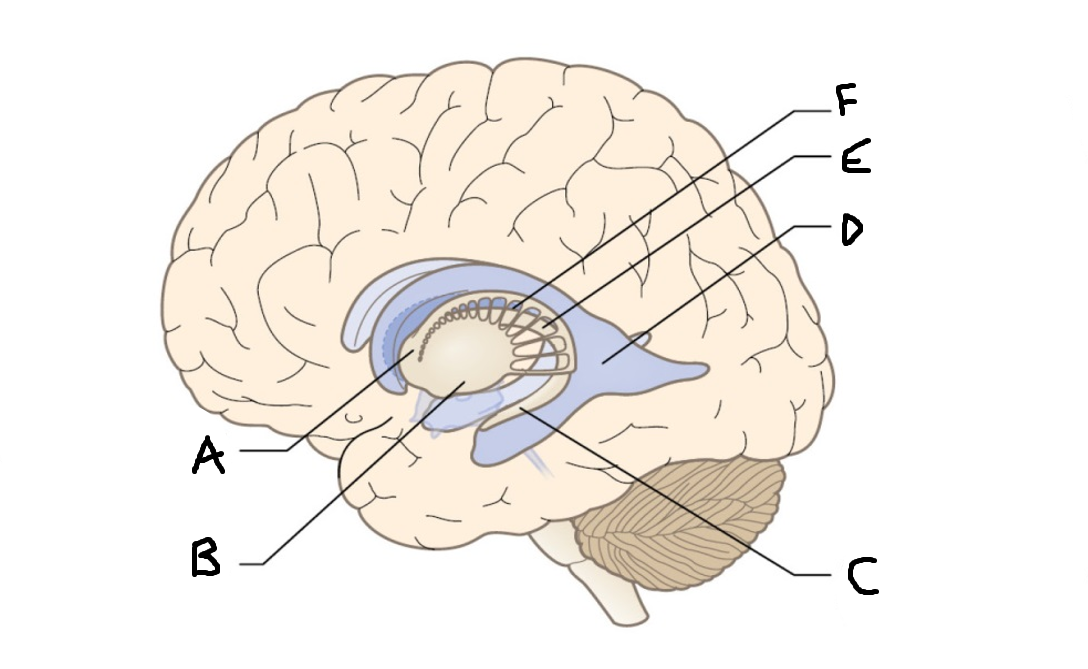

caudate nucleus head

A

Putamen

B

caudate nucleus tail

C

Lateral ventricle

D

caudate nucleus body

E

internal capsule

F